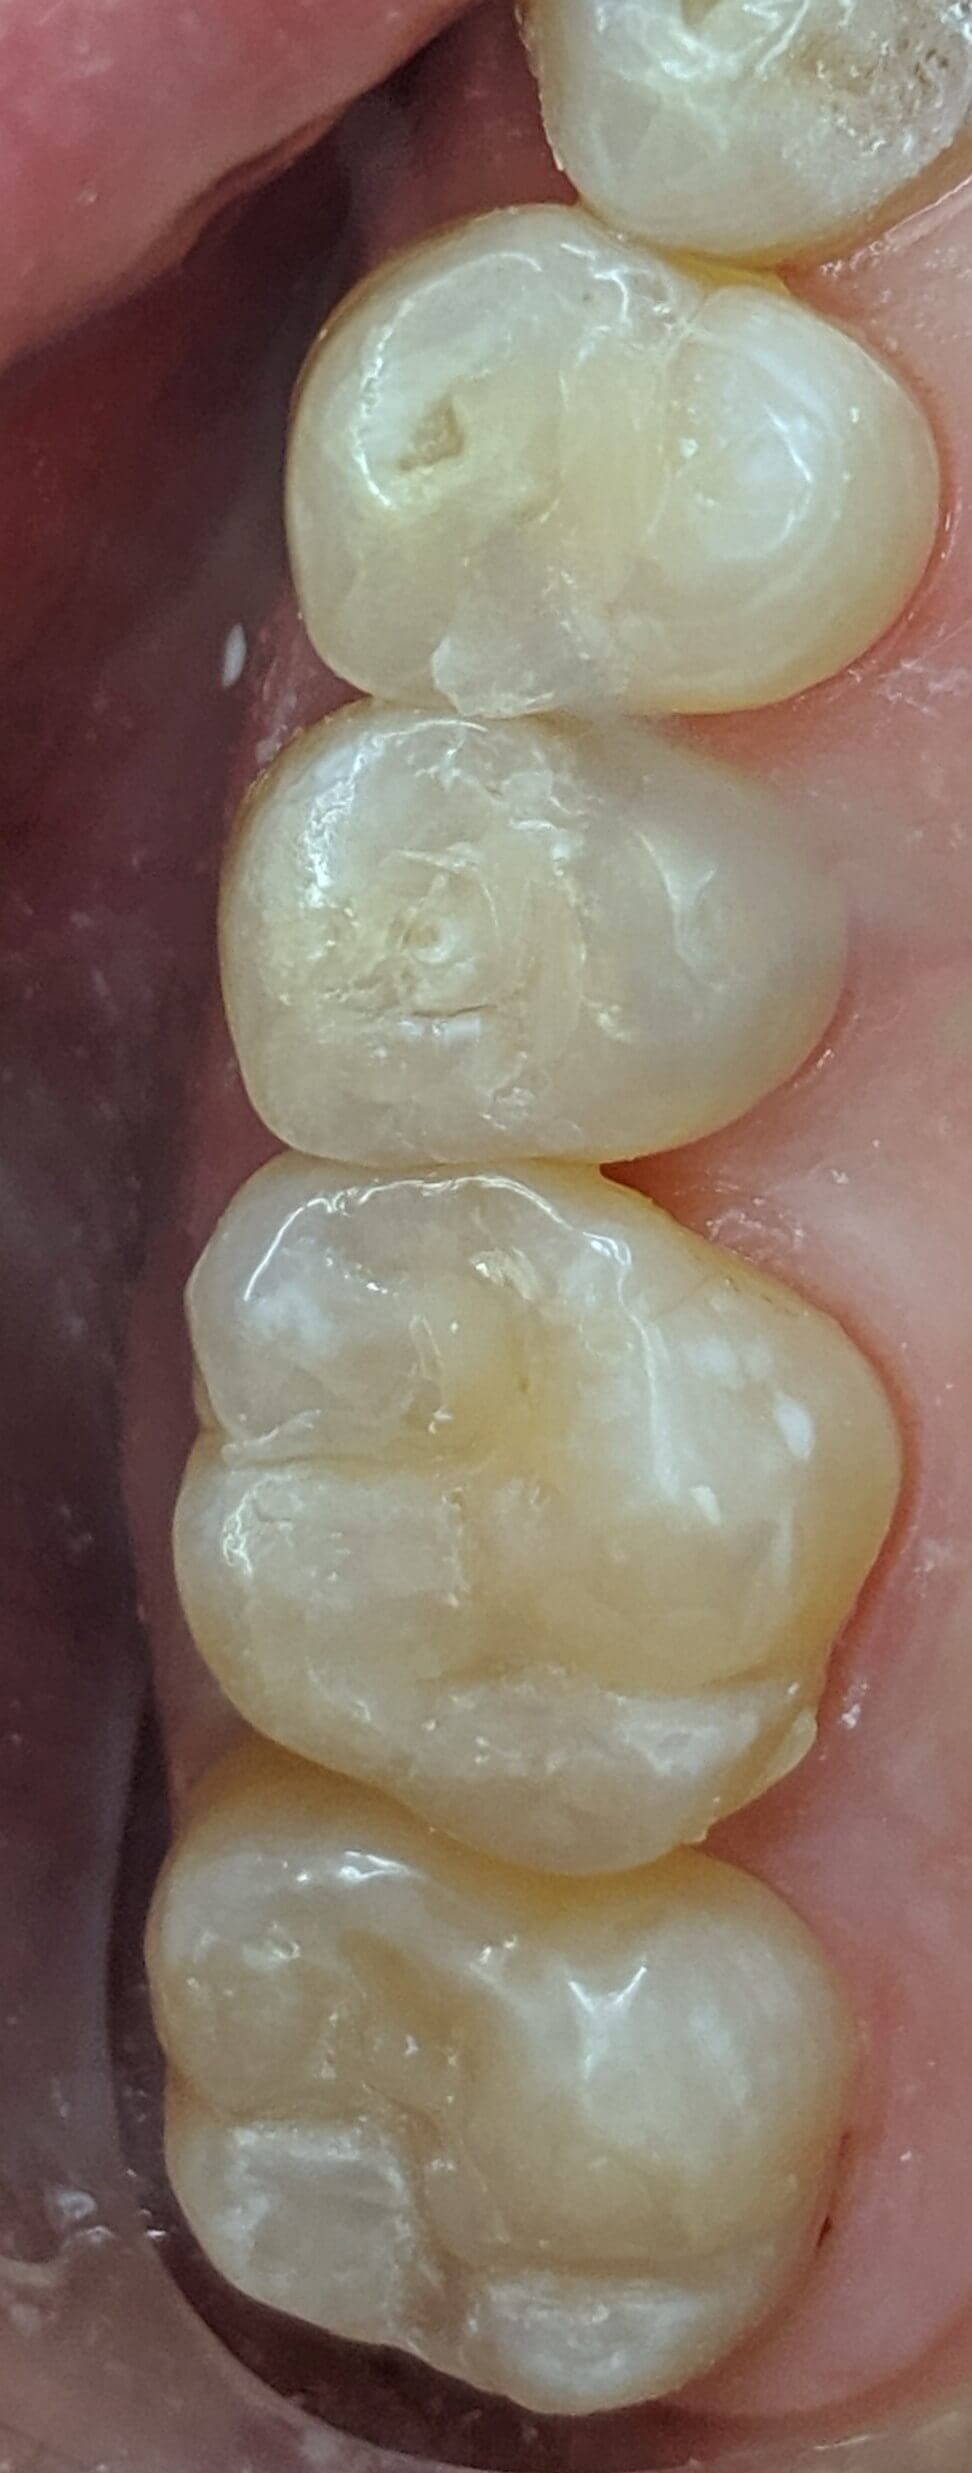

Tooth-colored fillings often fill in the decay in the enamel after it has been cleaned. Composite resin is a versatile material that can be used to treat other problems with your teeth, including cracks or enamel that has been worn down by teeth grinding (bruxism). Since the composite resin is colored to match your natural teeth, tooth-colored fillings can be used on both the front and back teeth for a seamless appearance. If you have metal fillings, talk to Dr. Kim or Dr. Chang about having them removed and replaced with tooth-colored fillings.

Getting a filling at Luminous Dental Studio is typically an easy process. The area surrounding the cavity will be numbed with a local anesthetic to minimize your discomfort. Other forms of sedation can be discussed if you have any fears or dental anxieties to help keep you at ease during the procedure. Once you are prepared, the decayed enamel is removed with a unique dental drill that Dr. Kim or Dr. Chang will select based on where the cavity is located in the tooth and the level of decay. After the enamel is removed and the tooth is cleaned, the cavity will be filled with the composite material and set with a special light. Dr. Kim or Dr. Chang will polish the filling so it feels comfortable and matches your natural teeth.